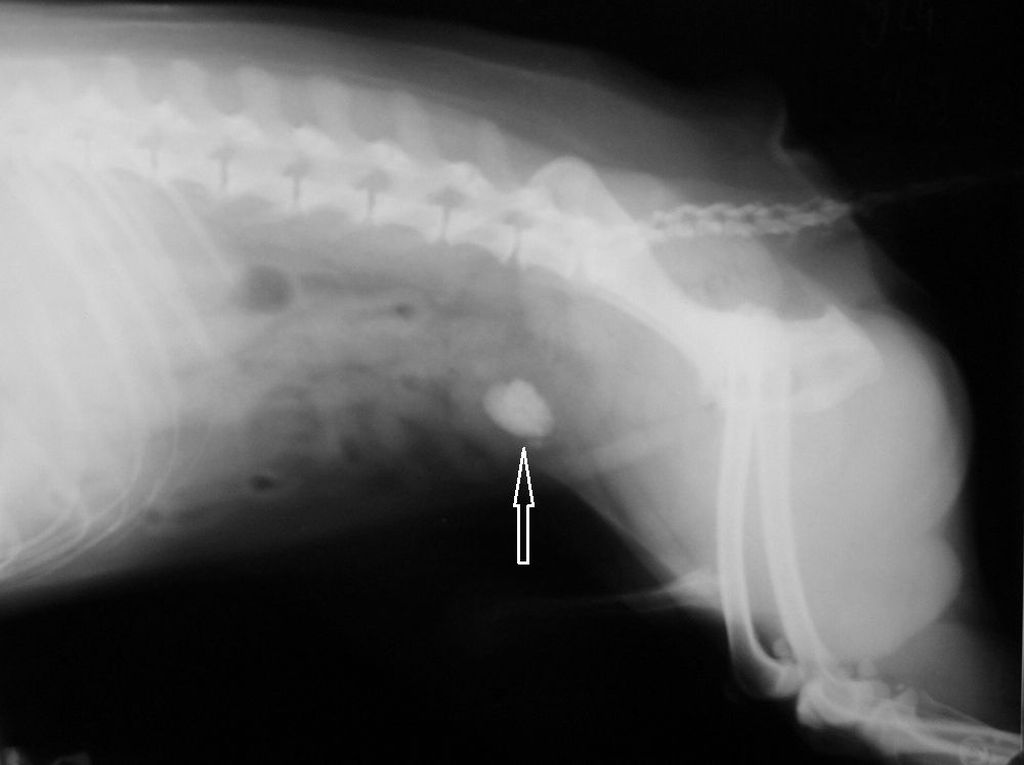

Струвиты у кошек что это

Струвиты у кошек что это 108 фотографий